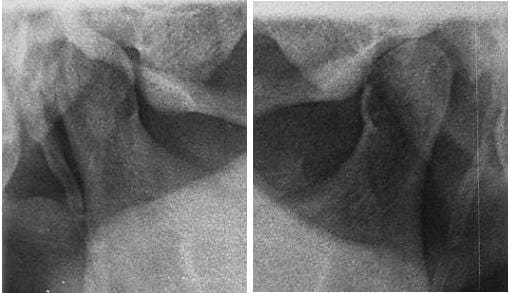

03/07/2006 à 23h05

Super tes photos solene,

la mise en occluseur me parait erronée avec ce type d'abrasions les incisives devraient être en contact, mais pas grave l'essentiel c'est l'aperçu. ,

Anomalies à vérifier:

malposition articulaire,

bout à bout de convenance.

Condyle D photo

Axe pano/ modèles Photo.